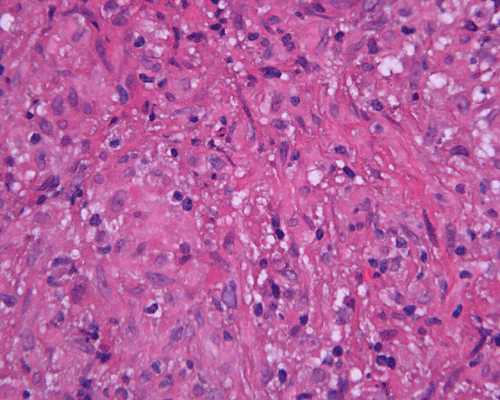

Paraffin sections: The entire volume of the tissue is made up of a granulomatous inflammation with poorly formed granuloma (Panel F, G, and H). The density of the lymphocytes is variable in different areas. In some areas, there is a rather intense lymphocytic infiltration accompanied by scant atypical cells with enlarged nulcei and prominent nucleoli (arrows in Panel I and J, Panel J is a higher magnification of Panel I). These atypical cells are quite easy to be missed. No microorganisms were identified by acid fast stain, PAS stain or GMS stain. The lymphocytes but not the atypical cells are positive for CD20 (Panel K) or CD3 (Panel L). The granulomatous background is strongly positive for CD68 (Panel M). Only rather faint positive staining for placental alkaline phosphatase (PLAP) is demonstrated and the interpretation is difficult as they are present in areas with crush artifact (Panel N). Many of the large, atypical cells are positive for CD117 (c-kit) (Panel O).

Intracranial germinoma is histologically identical to ovarian dysgerminoma and testicular seminoma. There is a tendency to infiltrate adjacent structures and to spread throughout the ependyma, the ventricular system and subarachnoid spaces. Microscopically, they consist of nests, lobules, cords, and/or sheets of large round tumor cells with well-defined borders, clear to pale cytoplasm with artifactual vacuolization, round and centrally located nuclei with open chromatin and prominent round or bar-shaped nucleoli. The cytoplasm is glycogen-rich, making these cells periodic acid-Schiff (PAS)–positive and diastase sensitive. These tumor cells are mitotically active. Atypical mitosis, however, is not a common finding. Necrosis is usually not prominent. In the most classic histologic picture, clusters and cords of large germinoma cells are separated by a dense, lymphocytic infiltration admixed with some macrophages and a delicate fibrovascular network. Plasma cells may be found. At medium-power magnification with hematoxylin and eosin stain, the contrast between the smaller, darkly staining lymphocytes and the larger, pale staining cytoplasm of neoplastic cells is virtually pathognomonic. The amount of inflammatory cells can have wide variations among different tumors. In some occasions, the large germinoma cells are difficult to be found and the overall picture may suggest a lymphoma. Syncytiotrophoblastic cells can also be present. These cells should not be mistaken as evidence of choriocarcarcinoma.

Germinomas can elicit an atypical gliosis in the surrounding glial tissue which may be confused with malignant glial neoplasms. This is true particularly of specimens taken from the periphery of the germinoma. The tumor may appear as a desmoplastic tumor. The inflammatory response may be problematic in reaching a histologic diagnosis, especially in small biopsies, as macrophages can be difficult to distinguish from a non-seminomatous neoplastic component.

Granulomatous changes are common findings in germinomas and intracranial germinomas follow this general trend 3, 4, 5. It can be extensive. This feature is particularly problematic in neuropathologic when stereotactic biopsy is performed and the amount of tissue available for examination is limited as illustrated in this case. During intraoperative consultations, a frozen section diagnosis of granulomatous inflammation should prompt additional sampling as isolated granulomatous inflammation of infectious origin and sarcodosis are quite uncommon in the pineal gland.